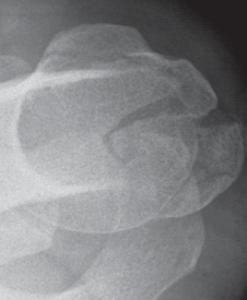

Der klassische Verschleiß des Schultergelenkes tritt im Vergleich zum Hüft- und Kniegelenk beim älteren Menschen seltener auf. Hierbei erfolgen eine Zerstörung des Gelenkknorpels und die Deformierung der Gelenkflächen, die zu einer schmerzhaften Bewegungseinschränkung des Schultergelenkes führen (Abb. 34, 37).

Das Schultergelenk wird häufig im Verlauf einer rheumatischen Erkrankung befallen. Die operative Therapie orientiert sich am Verlauf der Erkrankung. Im Stadium der Gelenkentzündung mit hauptsächlichem Befall der Weichteile (Gelenkschleimhaut, Gelenkkapsel, Rotatorenmanschette) ist ein arthroskopisches Debridement mit Entfernung der Gelenkschleimhaut (Synovia) und des Schleimbeutels das Verfahren der Wahl. Schreitet die Erkrankung jedoch weiter fort und greift auf den Gelenkknorpel und Knochen über, so sollte möglichst frühzeitig eine Prothese eingesetzt werden. Im frühen Stadium lässt dann eine so genannte Cup-Prothese einsetzen (Abb. 43).

Oberarmkopfnekrose